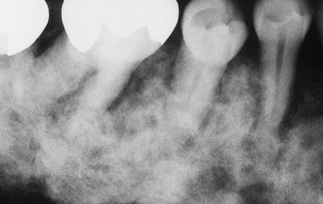

cherubism